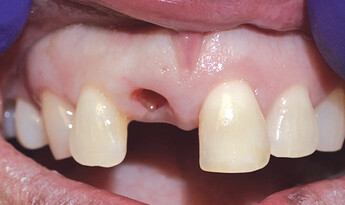

The patient presented with a failing tooth #8. After extraction, the socket shape resembled a triangle. Because of the round shape of the dental implant, there were gaps between the implant body and the alveolus which required grafting.

A temporary appliance was delivered and the site allowed to heal. After approximately three months, the healing abutment was removed and stability was checked with a Penguin RFA® A small amount of gingival recontouring was completed with a diode laser, and impressions were taken. The final BruxZir® Esthetic restoration was delivered, and final adjustments were made.